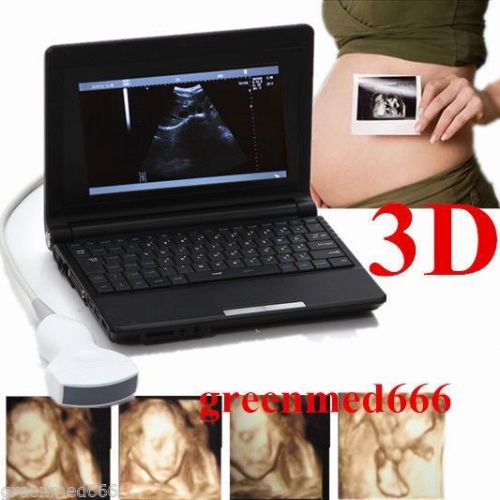

Laptop Ultrasound Scanner Digital Mobile Diagnostic System +Convex Probe+3D CE

3D Working Station Digital Portable Ultrasound Scanner machine CONVEX Probe 2015

3D Digital Portable Ultrasound Scanner machine+CONVEX &Transvaginal Probe FDA CE